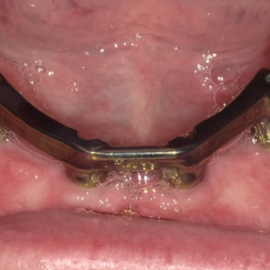

The process of implant dentures begins with a thorough dental examination and consultation with a dental implant specialist. During this visit, different options are discussed, and a personalized treatment plan is created based on your needs and medical history.

Receiving implant dentures is a multi-step process that includes placing the dental implants and securely attaching the dentures with precision.